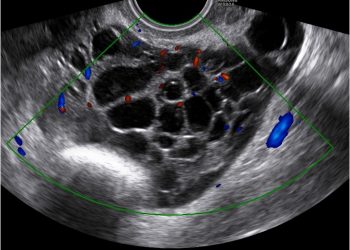

Guida al Counseling di Agosto 2022: endometriosi

Cari colleghi, vi presentiamo la guida al counseling di Agosto relativa alla diagnosi e alla gestione dell'endometriosi Potrete scaricarla cliccando...